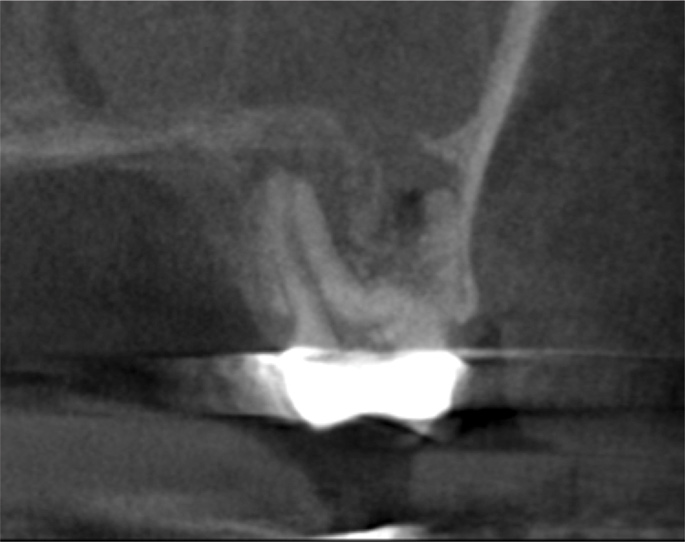

For patients suffering from MSEO, radiographs will reveal a periapical radiolucency with adjacent opacification in the maxillary sinus.12 Additional radiographic findings associated with MSEO include periapical mucositis and periapical osteoperiostitis (PAO). Periapical mucositis refers to mucosal thickening or dome-shaped soft-tissue expansion on the floor of the sinus directly adjacent to the infected root apex.PAO refers to the reactive osteogenesis caused by a local periosteal reaction that expands the sinus periosteum and displaces it upward into the sinus. It appears as a radiopaque "halo" surrounding the root apex (Figure 2 through Figure 4). PAO may be symptomatic and/or accompanied by adjacent mucosal edema and elevated sinus fluid levels.9 If left untreated, PAO can progress and result in a direct communication between the root apex and maxillary sinus.6,13 Unless bilateral odontogenic pathosis is found, the sinus opacifications will usually be unilateral and centered around the odontogenic source. Complete unilateral sinus opacifications may be missed on the CBCT images typically used in endodontics due to their limited or focused field of view (Figure 5). In cases involving complete unilateral sinus opacification, referral to an ENT or oral surgeon is essential to rule out invasive fungal infection or malignancy.2,17,24

(3.) Sagittal slice of CBCT image of the same tooth displaying PAO or “halo lesion” with associated mucositis.

Figure 3